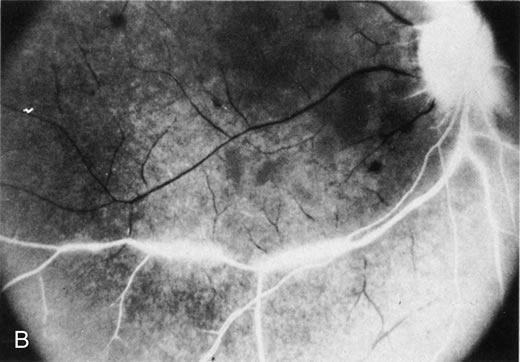

The finding of retinal vascular changes in patients with SLE correlates with the activity of the disease.214 The relationship of cotton-wool spots alone to CNS lupus has been debated, but to date no relationship has been established. Most experts feel that the finding of cotton-wool spots does not indicate the presence of CNS lupus. A much less frequent, severe retinal vasoocclusive disease has been described and does appear to be associated with CNS lupus, in particular, diffuse CNS dysfunction, such as an organic brain syndrome.214–223 This more severe retinal vasoocclusive disease may present as a central retinal artery occlusion, central retinal vein occlusion, branch artery occlusion, or most frequently, a diffuse retinal vasoocclusive process (Fig. 5), sometimes called retinal vasculitis. Although this last process sometimes has been called retinal vasculitis, the exact pathogenesis may not be true vasculitis. Cases of severe retinal vasoocclusive disease in SLE in association with the lupus anticoagulant also have been reported, and the retinal disease in these cases is presumed to be secondary to this autoantibody (Fig. 6).190,191 The prognosis for vision with this diffuse retinal vascular disease is poor and retinal neovascularization commonly develops. Panretinal photocoagulation may be of value in the treatment of the neovascularization of severe lupus retinopathy. Approximately 50% of eyes affected with this severe vaso-occlusive disease become blind. Although visual loss is common in those patients with severe retinal disease, in the more common mild retinopathy visual loss is unusual.223

Fig. 5. A. Fundus photograph and B. fluorescein angiogram, demonstrating diffuse vaso-occlusive disease in a patient with systemic lupus erythematosus. Fluorescein angiogram shows extensive nonperfusion of the retina. (Jabs DA, Fine SL, Hochberg MC, et al: Severe retinal vaso-occlusive disease in systemic lupus erythematosus. Arch Ophthalmol 1104:558, 1986. Copyrighted 1986, American Medical Association. Reprinted with permission.)

Fig. 6. A. Fundus photograph and B. fluorescein angiogram demonstrating diffuse vaso-occlusive disease in a patient with systemic lupus erythematosus. This is peripheral nonperfusion of the retina. The patient had anticardiolipin antibodies. (Jabs DA, Fine SL, Hochberg MC, et al: Severe retinal vaso-occlusive disease in systemic lupus erythematosus. Arch Ophthalmol 104:558, 1986. Copyrighted 1986, American Medical Association. Reprinted with permission.)